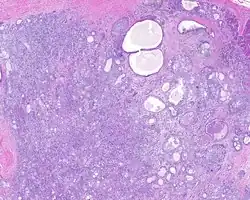

When reviewed by a pathologist, the findings are quite similar to fibrocystic changes of the breast, although they are different enough, that it is now recognized to actually represent a true neoplasm (clonal proliferation) through various studies.[5] Specifically, the lesions are usually well-circumscribed, containing lobules of haphazardly arranged ducts, myoepithelial cells, and acini that have abundant sclerosing or hyalinized fibrosis. Apocrine change is quite common in the ductal cells.[6] The ducts range from small ductules to cystically dilated spaces (more than 4 striated duct-widths across), often containing products of secretion or reactive histiocytes. A very curious and characteristic finding in all of the lesions is the presence of bright pink (eosinophilic) acinar granules (which are altered zymogen).